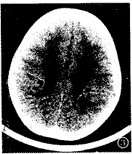

图3 重度PVL:侧脑室周围白质对称性稀少,外侧裂池部位脑沟加深, 脑灰质逼近侧脑室后角缘,与侧脑室缘距离消失,并突向侧脑室,侧脑室扩大,有切迹,边缘不规整。

3个月内复查CT 30例,CT表现异常19例,其中2个月内复查CT时,12例侧脑室后角或前、后 角周围白质内仍可见斑片状低密度灶。外部性脑积水(EH)1例,CT表现为:额顶区蛛网膜下 腔对称性增宽,宽度≥5mm,大脑半球间裂前部增宽,额顶区大脑沟增宽加深,脑基底池主 要是鞍上池增大,脑室不大或轻度扩大[5,6](图2)。脑室周围白质软化症(PVL)3 例,其中脑软化和脑萎缩1例,结合文献[7],PVL可分为轻、中、重3度,CT诊断 标准为:侧脑室周围白质明显对称性减少或消失,外侧裂池部位脑沟加深,脑灰质逼近侧脑 室缘,与侧脑室缘的距离甚小或消失,侧脑室不同程度扩大,以后角、三角区明显,侧脑 室缘不规整(图3),侧脑室后角或前、后角周围白质内可见斑片状低密度灶。脑积水2例,脑 软化1例。